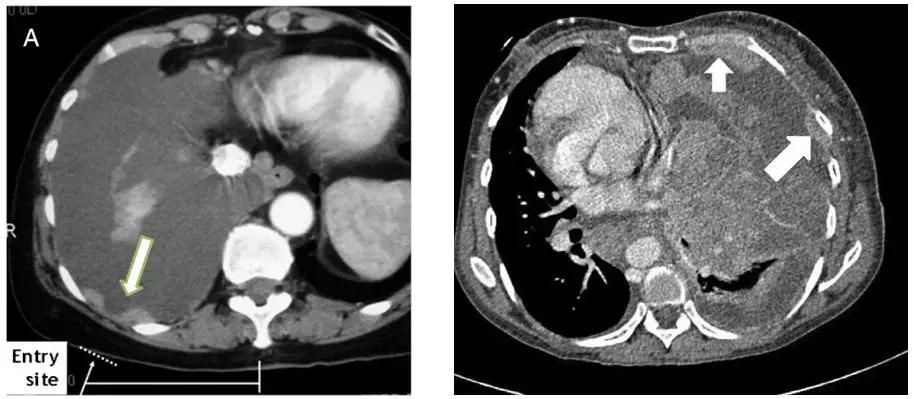

二、CT引导下胸膜活检

如下图,选择增厚、病变比较明显的地方进行穿刺,阳性率较高。

操作步骤比较简单

CT扫描确定胸膜增厚的区域,使用体表定位卡选取最佳进针点,设计好进针方向、深度和角度。穿刺点常规消毒铺巾后,使用同轴套针沿设计好的进针路径缓慢进针,达到计划深度后再次行CT扫描,如确定针尖已达到目标部位后,使用切割针进行穿刺活检。

男性,68岁,CT示:左下肺后基底段结节影伴左侧胸膜局灶性增厚。CT引导下胸膜穿刺活检证实为腺癌。